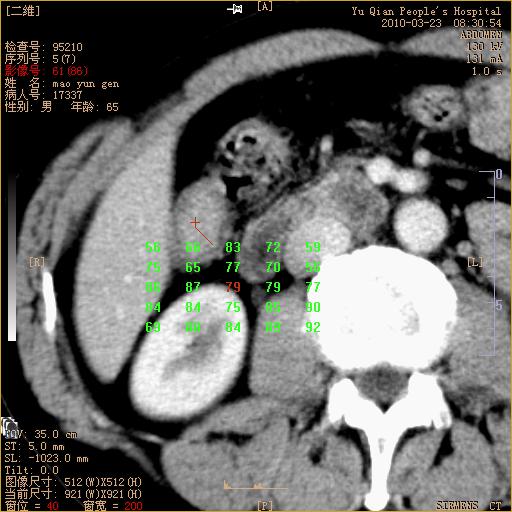

标题: CT25266:消瘦月余,前来肝部检查,请看看肠腔 [打印本页]

标题: CT25266:消瘦月余,前来肝部检查,请看看肠腔

肝区结肠占位,腺癌可考虑,建议肠镜活检。

升结肠肠壁增厚,不均强化,考虑升结肠腺癌可能性,建议肠镜检查。

1)考虑升结肠癌。2)右肾小囊肿。